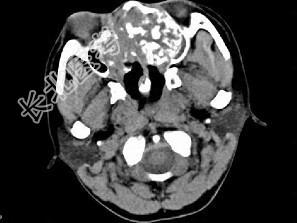

- 单项选择题男,26岁, 进行性鼻腔阻塞、流涕来院就诊,近两年持续性头痛、头晕.如图所示筛窦区占位灶应诊断为 ( )

A、脊索瘤伴左上颌窦炎

B、软骨瘤伴左上颌窦炎

C、骨化性纤维瘤伴左上颌窦炎

D、骨结核伴左上颌窦炎

E、骨纤维异常增殖症伴左上颌窦炎